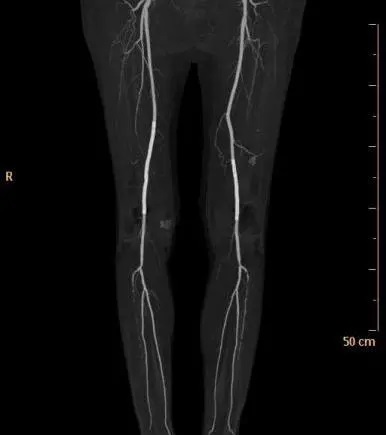

▲ 术后复查CTA,双下肢动脉血流通畅良好

王兵教授及崔文军主任进行科室讨论给病人制定了“杂交手术”治疗方案,经右侧股动脉切开取栓,然后同时处理双侧病变,手术取出一部分血栓,放置了2枚支架,成功将两条腿的血管成功打通。手术后,经过护理后,顺利出院,走路基本恢复正常。